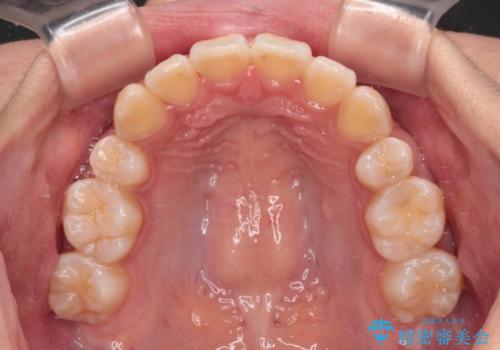

- 前歯のデコボコやクロスバイトと上顎の前突感による口の閉じにくさを気にして来院された患者様です。

目立たない装置を希望されたので、上顎が裏側装置のハーフリンガルを選択し、上下左右の小臼歯(計4歯)を抜歯して矯正治療を行うこととしました。

表側のワイヤー矯正に比べると治療期間は長く、費用も高額となりますが、どうしても目立たせたくないという方にはお勧めの抜歯矯正です。